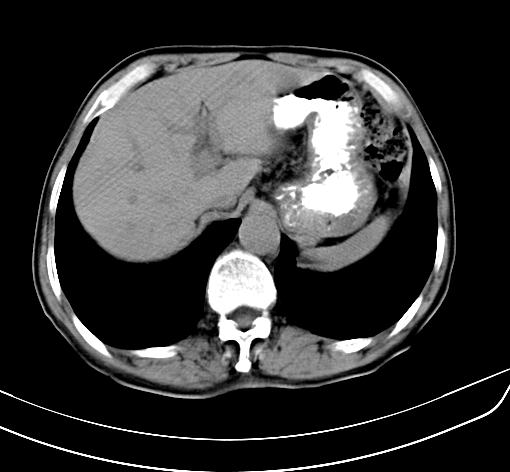

病人 男 70 咳嗽 胃部不适 2月余

胆囊壁增厚,与临近肝实质边界不清,临近肝实质内可见大片边界不清之低密度区,肝门区密度亦有减低,部分结构不清,尾叶前方可见块状影,肝右叶可见多枚边界不清之圆形低密度区,肝内胆管扩张征象,结合病史考虑1胆囊癌肝内转移,肝门区淋巴结转移,门脉癌栓待排2肝内胆管扩张3建议增强扫描

肝脏多发大小不等低密度灶,边界不清,肝门区结构不清,肝内胆管轻度扩张,胆囊密度不均匀,内见软组织样密度影,与相临肝脏边界不清.考虑:1、胆囊ca侵犯肝脏并肝内多发转移,肺上也有结节影,转移?建议强化扫描.2、胃充盈不好,如怀疑有病变最好建议做相关检查.

胆囊壁增厚,周围模糊不清,肝内多发低密度影,胃充盈欠佳,胃壁增厚,外形尚规整,考虑胆囊炎、胆囊癌肝内转移?建议胃肠道进一步检查或增强扫描。